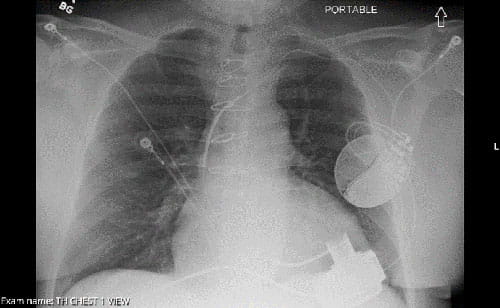

LVAD device xray X-ray with LVAD.